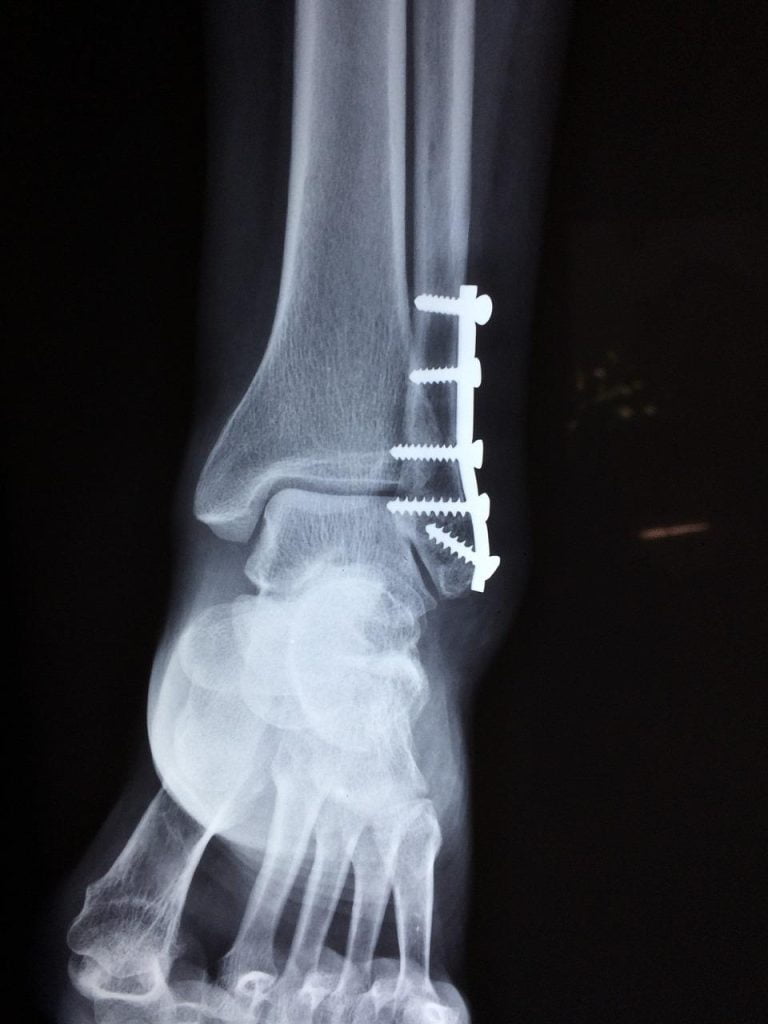

- Diagnostische beeldvorming: Geavanceerde beeldvormingstechnieken zoals röntgenfoto’s, MRI-scans en CT-scans worden gebruikt om orthopedische aandoeningen nauwkeurig te diagnosticeren en de beste behandelingsaanpak te bepalen.

In Emmen worden geavanceerde beeldvormingstechnieken zoals MRI, CT-scans en echografie gebruikt voor nauwkeurige diagnose en planning van orthopedische behandelingen. Deze technologieën stellen zorgverleners in staat om de anatomische structuren en pathologieën in detail te visualiseren, waardoor gepersonaliseerde behandelplannen kunnen worden ontwikkeld.